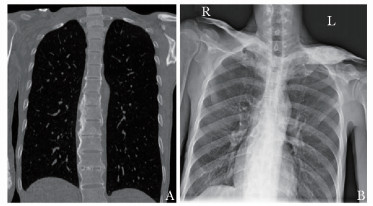

• 摘要: SAPHO综合征是一类以骨关节和皮肤病变为特点的罕见临床综合征,即出现滑膜炎(synovitis)、痤疮(acne)、脓疱病(pustulosis)、骨肥厚(hyperostosis)和骨炎(osteitis)等一系列病变。本文报道一例具有31年病史的非典型SAPHO综合征患者,经详细的诊断及鉴别诊断以及合理的诊疗方案的实施,最终患者病情获得明显改善。通过回顾并总结SAPHO综合征的临床诊疗特点,以及对该病例的讨论分析过程,充分体现了多学科诊疗在罕见病诊治中的有效性及必要性。

Abstract: The SAPHO syndrome is a rare disease characterized by osteoarticular and dermatological manifestations. Here we reported an atypical case of SAPHO syndrome for 31 years. A multidisciplinary team made the diagnosis and differential diagnosis of the patient's osteoarticular and dermatological lesions. Subse-quently, suitable treatment was initiated and the patient's condition was significantly improved. At last, we reviewed and sum- marized the characteristics of diagnosis and treatment of SAPHO syndrome. The effectiveness and necessity of multidisciplinary treatment were demonstrated by the discussion and analysis of this rare disease.